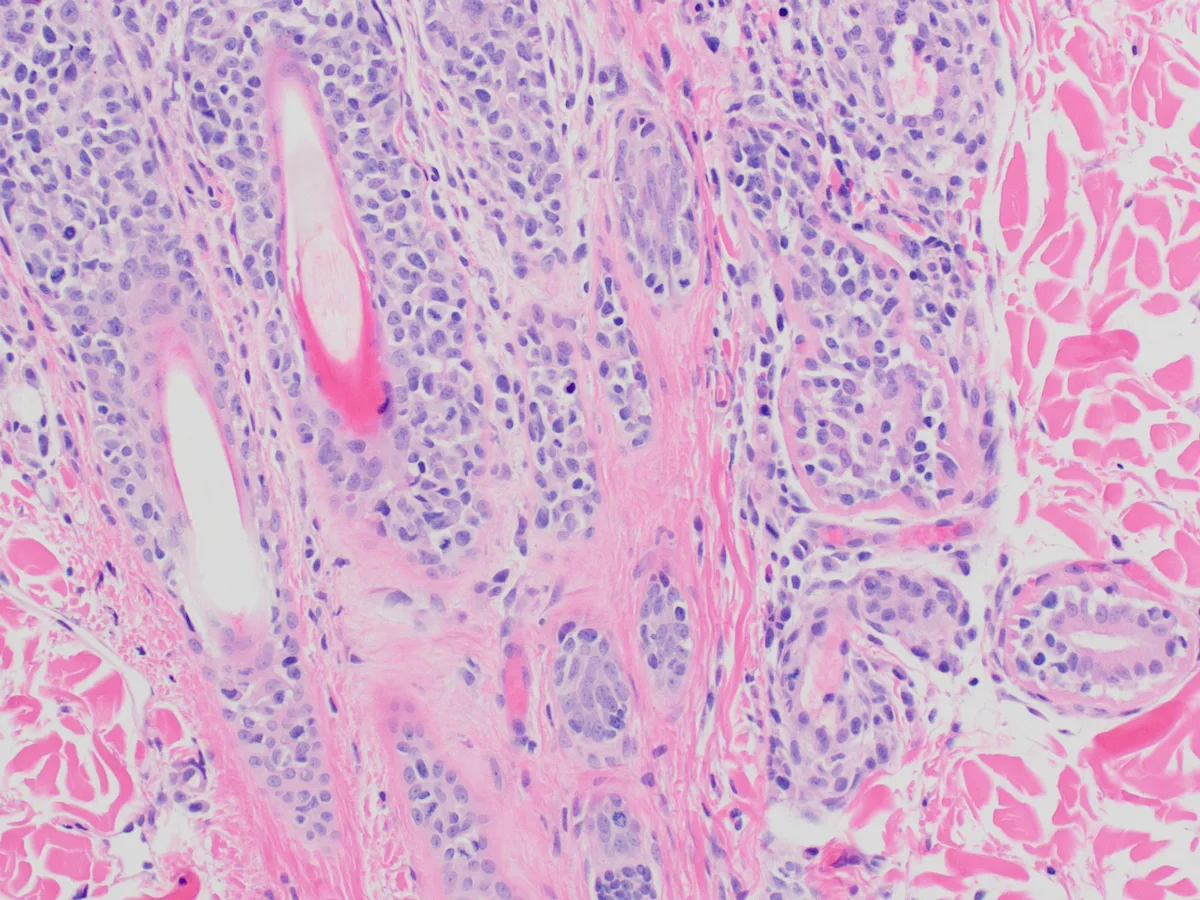

Histopathology showed round cells in the dermis, subcutis, follicular epithelia, apocrine glands, and epidermis (Figure 3) that occasionally formed small intraepidermal nests (ie, Pautrier's microabscesses, which are enlarged, atypical T-lymphocytes forming aggregates or found diffusely within the epidermis). Neoplastic round cells had distinct cell margins and central nuclei with finely stippled, normochromatic chromatin and 1 to 2 small nucleoli. Mitoses ranged from 3 to 16 per high-power field (40×), with 64 mitotic figures counted in 10 randomly selected high-power fields.

Histopathology showing infiltration of the epidermis by neoplastic lymphocytes. Image courtesy of Dr. Shannon Martinson

Inflammation is characterized by infiltration of neoplastic T lymphocytes with a tropism for the epidermal or mucosal epithelium, as well as adnexal structures, especially the follicular wall (Figure 4).7,12 Pautrier’s microabscesses (intraepithelial neoplastic lymphocytes diffusely in the epidermis or in aggregates) may be noted.7 Neoplastic lymphocytes that infiltrate apocrine sweat glands occur in 70% of cases and are considered diagnostic (Figure 5).6,7